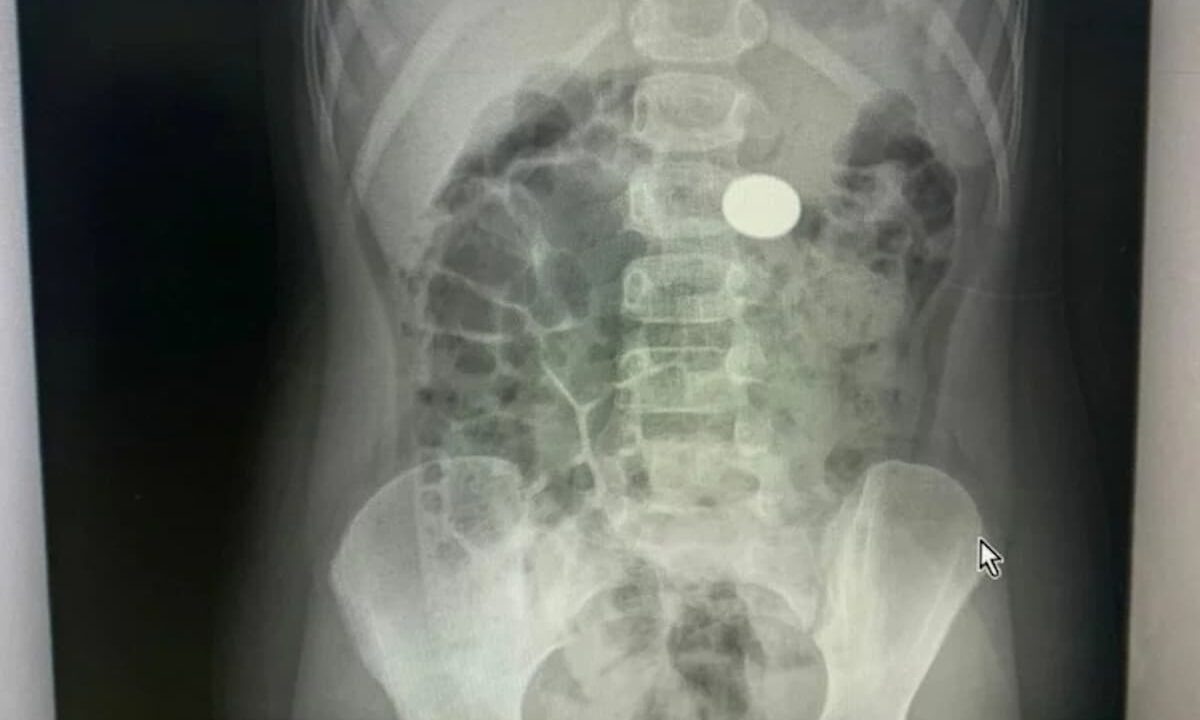

В отделении эндоскопии Туапсинской районной больницы № 1 поступила девочка в возрасте 6 лет.

Во время рентгена медики обнаружили инородный предмет в желудке девочки. Выяснилось, что ребенок проглотил рублевую монету.

По словам завотделением эндоскопии Гора Саакяна, врачи двое суток готовились к процедуре. Достать монету удалось без скальпеля при помощи эндоскопа. Сейчас девочка чувствует себя хорошо.